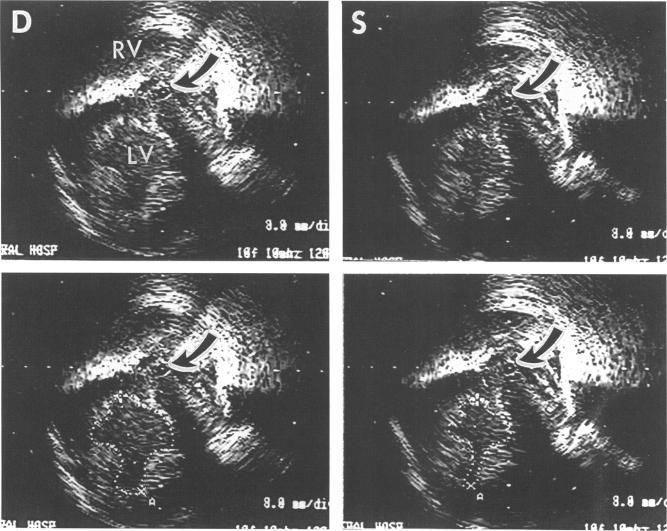

To evaluate the feasibility and ability of percutaneous transvenous intracardiac echocardiography (ICE) to image the left ventricle (LV) and monitor its function from the right ventricular (RV) cavity.

A 10 MHz catheter was advanced into the RV from the jugular vein and positioned along the septum at the LV papillary muscle level in five dogs. The catheter was manipulated until a stable catheter position along the septum, which provided on-axis images of LV, was obtained. Different states of LV size and systolic function (n = 80) were created with dobutamine or esmolol, both in the presence and absence of coronary stenoses. LV stroke area (cm2) obtained by ICE was measured at the mid-ventricular level and compared with stroke volume (cm3) obtained simultaneously with a transaortic flow probe. LV end diastolic, end systolic, and stroke areas obtained by ICE were also compared with those obtained by short-axis epicardial echocardiography.

In 96% of the stages, short axis images of the LV could be obtained and measured by ICE. LV end diastolic, end systolic, and stroke areas measured by ICE were not significantly different from epicardial echocardiographic values. Stroke area correlated with stroke volume in each dog (mean correlation coefficient 0.79 (SEE 0.19) cm2) (P < 0.001).

评估经皮经静脉心腔内超声心动图(ICE)从右心室(RV)腔对左心室(LV)成像并监测其功能的可行性和能力。

将一根10MHz的导管经颈静脉插入右心室,并在五只犬的左心室乳头肌水平沿室间隔定位。操作导管直至获得沿室间隔的稳定导管位置,该位置可提供左心室的轴位图像。在有和没有冠状动脉狭窄的情况下,使用多巴酚丁胺或艾司洛尔创建左心室大小和收缩功能的不同状态(n = 80)。通过ICE在心室中部水平测量左心室的每搏输出面积(cm²),并与经主动脉流量探头同时获得的每搏输出量(cm³)进行比较。通过ICE获得的左心室舒张末期、收缩末期和每搏输出面积也与短轴心外膜超声心动图获得的结果进行比较。

在96%的阶段中,ICE能够获得并测量左心室的短轴图像。ICE测量的左心室舒张末期、收缩末期和每搏输出面积与心外膜超声心动图的值无显著差异。每只犬的每搏输出面积与每搏输出量相关(平均相关系数0.79(标准误0.19)cm²)(P < 0.001)。